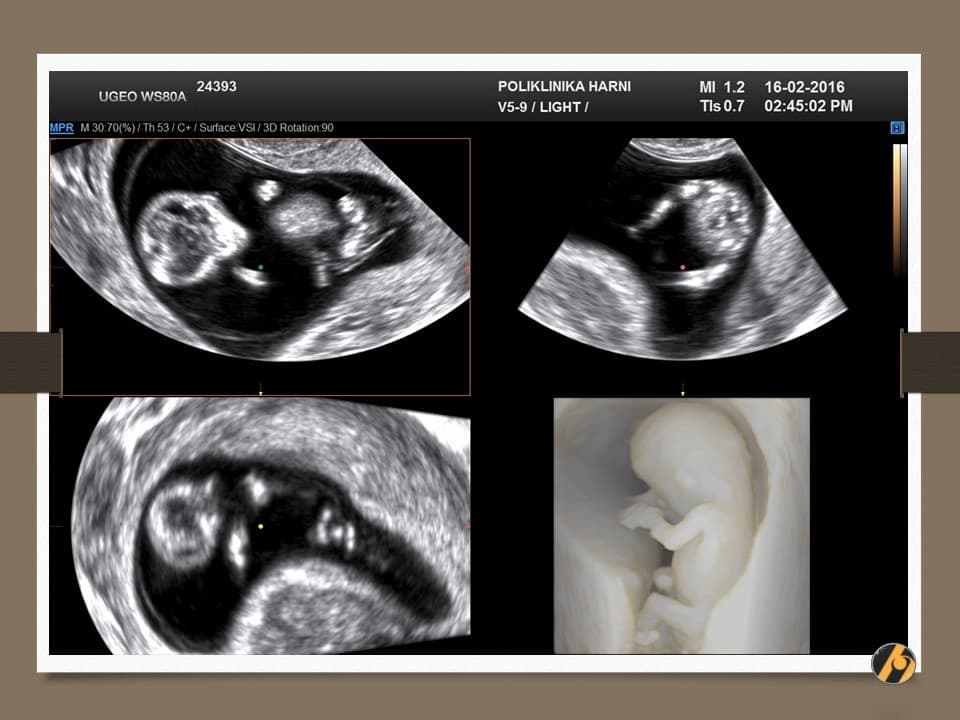

Konačno je dovršen veliki posao, završena je embriogeneza i vaša beba je kompletno razvijena. Od sada pa do konca trudnoće najveće promjene se odnose na dobitak na težini i rast bebe. Beba se od sada više ne naziva embrij, nego fetus.

Premda je dovršena embriogeneza, organogeneza i fetalni rast se nastavljaju ubrzanim tempom, pa je beba u zadnja dva tjedna udvostručila svoju težinu.

Nastavlja se oblikovanje lica koje je sve više nalik ljudskom licu. Razvitkom noktiju na rukama i nogama završava se razvitak prstića. Beba je veoma pokretna i kod ultrazvučnog pregleda se zapažaju nagli i snažni pokreti tipa trzaja - pokreti su spontanog karaktera, ali bez volje djeteta. U ovo vrijeme je kontrola pokreta djeteta još uvijek podređena živčanim središtima u leđnoj moždini, a moždani centri za koordinaciju pokreta još nisu razvijeni.

U ovome tjednu se crijeva u potpunosti smještaju u trbušnu šupljinu i ukoliko se prije vidjela omphalocoela (prisustvo crijeva u pupčanoj vrpci), sada se ta slika gubi. Formirano je i raspoznatljivo vanjsko spolovilo, koje se standardnim ultrazvučnim tehnikama još neko vrijeme neće moći raspoznati.

Vaša beba dugačka je oko 6.5 cm, a teška 10 - 15 g.